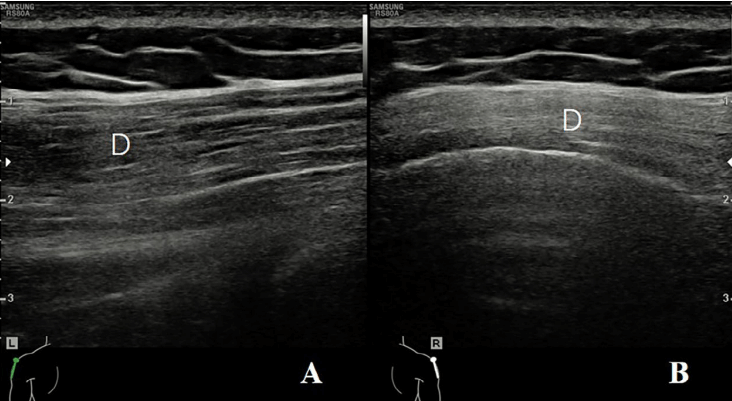

探头的位置根据三个解剖标志来确定:四边孔、肩胛下肌的前方和腋动脉的后方。1)四边孔:由上方的小圆肌、下方的大圆肌、内侧的肱三头肌长头和肱外侧的骨外科颈构成。在评估这个区域时,患者取坐位,肩部处于中立位置。探头沿纵向放置在肩胛骨的外缘和肩胛骨下角下方,以显示冈下肌和小圆肌的短轴切面(图2A)。探头沿着矢状面向外侧移动,直到出现肱三头肌长头腱(图2B)。在这一切面上,小圆肌位于肱三头肌长头的头侧和浅方,大圆肌位于足侧和深方。探头继续向外侧移动,直到出现肱骨干(图2C)。在此切面上,腋神经(AN)和旋肱后动脉位于由头侧的小圆肌(Tm)、足侧的肱三头肌长头(Tr)、浅方的三角肌(D)和深方的肱骨干围成的空间内。通过调整探头,可以更清楚地显示神经血管束(图2D)。

图2A:探头沿着矢状面放置在肩胛骨的外缘和肩胛骨下角下方,以显示冈下肌(InfraS)和小圆肌(Tm)的短轴。三角肌(D)位于冈下肌(InfraS)和小圆肌(Tm)的表面。

图2B:探头向外侧移动,直到出现肱三头肌长头腱(Tr)(图1B)。在这个水平上,小圆肌(Tm)位于肱三头肌长头的头侧和浅方,大圆肌(Tmj)位于足侧和深方。

图2C:探头继续向外侧移动,直到出现肱骨干(图1C)。在此切面上,腋神经(AN)和旋肱后动脉(白色箭之间)位于由头侧的小圆肌(Tm)、足侧的肱三头肌长头(Tr)、浅方的三角肌(D)和深方的肱骨干围成的空间内。

图2D:通过调整探头,可以更清楚地显示腋神经(向上箭)和旋肱后动脉(向下箭头)。